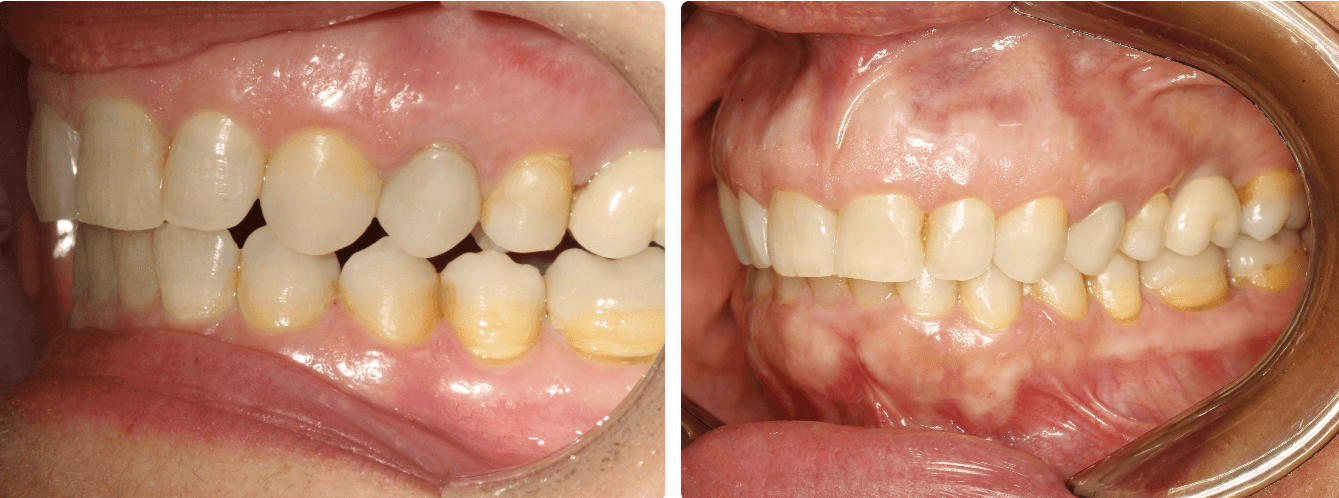

Mordida Cruzada

Correções desse tipo de maloclusão é mais previsível quando associada a inclinação, quando é necessaria movimento de corpo afim de vestibularizar o dente, a previsibilidade cai, precisamos de attachments e a chance de retração aumenta.

Descruzar mordida em regiões de extremos livres são mais imprevisíveis devido à falta de ancoragem na região, provavelmente attachments serão associados.

Casos que envolvem correção de mordida cruzada, são longos e podem precisar de mecânicas elásticas para melhor previsibilidade dos movimentos.

Casos de mordida de Brodie muito provavelmente precisaram de um plano ez 24

Casos que necessitam de expansão para descruzar a mordida, utilizamos a técnica de estagiamento “butterfly”. Você pode entender mais sobre nossas técnicas de estagiamento em Padrões de movimentação com os alinhadores .

Quando a correção da mordida cruzada envolve mais retração de um arco do que expansão, reflita sobre como o espaço sera obtido, desgastes, distalização sequencial ?